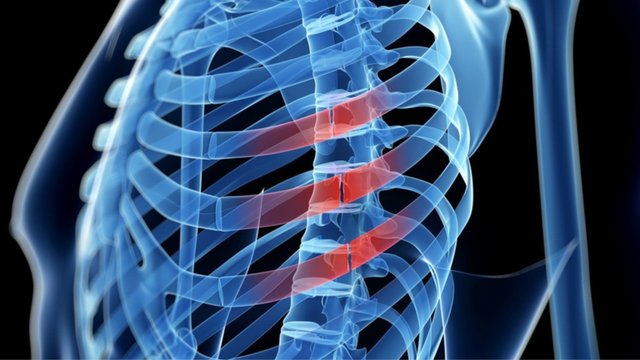

Rạn xương